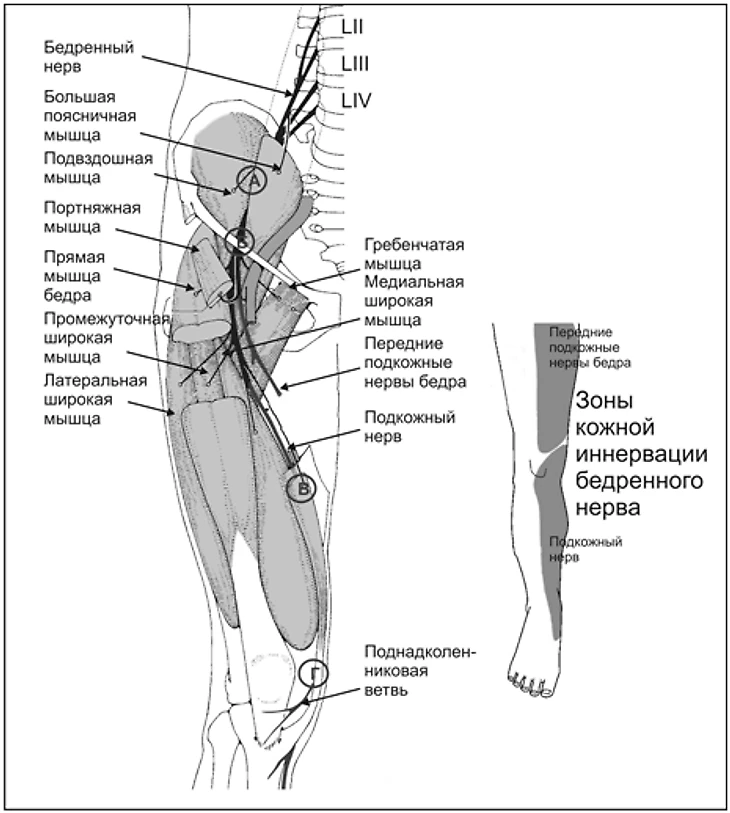

Несмотря на очень похожие симптомы, тактика лечения радикально отличается в зависимости от причин боли. Шпинев говорит о длинной приводящей мышце бедра (m. adductor longus). На рисунке выше отмечены мышцы, которые могут вызвать аналогичные симптомы – как видите, вариантов много. Чтобы не запутаться, разработана классификация под названием Дохийское соглашение (Афганистан тут ни при чем). Рассмотрим травму Миранчука с помощью этого гайда.

Шпинев говорит о повреждении приводящей мышцы, и мы уже поняли, что это «истинная паховая боль» по установленной классификации. Причинами могут быть спазм или повреждение мышцы и ее сухожилия. Кроме того, в толще этих мышц находятся ветви бедренного и запирательного нерва, и в случае травмы мышц бедра из-за спазма или отека может возникать их сдавление или даже повреждение.